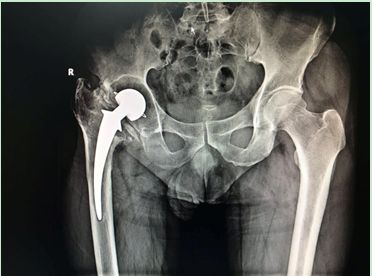

疼痛性假體松動是翻修手術最常見的適應證,典型表現是起步時疼痛,髖臼假體的松動通常引起腹股溝區(qū)的疼痛,而股骨假體的松動則導致大腿或膝部疼痛。該患者27年前因髖關節(jié)結核行髖關節(jié)置換術,近年來出現患肢短縮及行走疼痛,在我院診斷為“全髖關節(jié)置換術后假體松動”。

術前X線:髖關節(jié)假體已松動,假體周圍大量骨溶解

但是“松動”并不意味著假體容易取出,大多數情況下需要用各種方法用力將假體取出。同時清除初次手術中的骨水泥是髖關節(jié)翻修手術中最為費時和危險的。而由于磨損松動或者感染引起骨缺損是髖關節(jié)翻修中的最主要問題。該患者術前X線及CT檢查顯示存在大量的骨缺損,我科率先使用鈦合金骨小梁填充塊重建髖臼,完美的解決了髖臼的骨缺損問題。